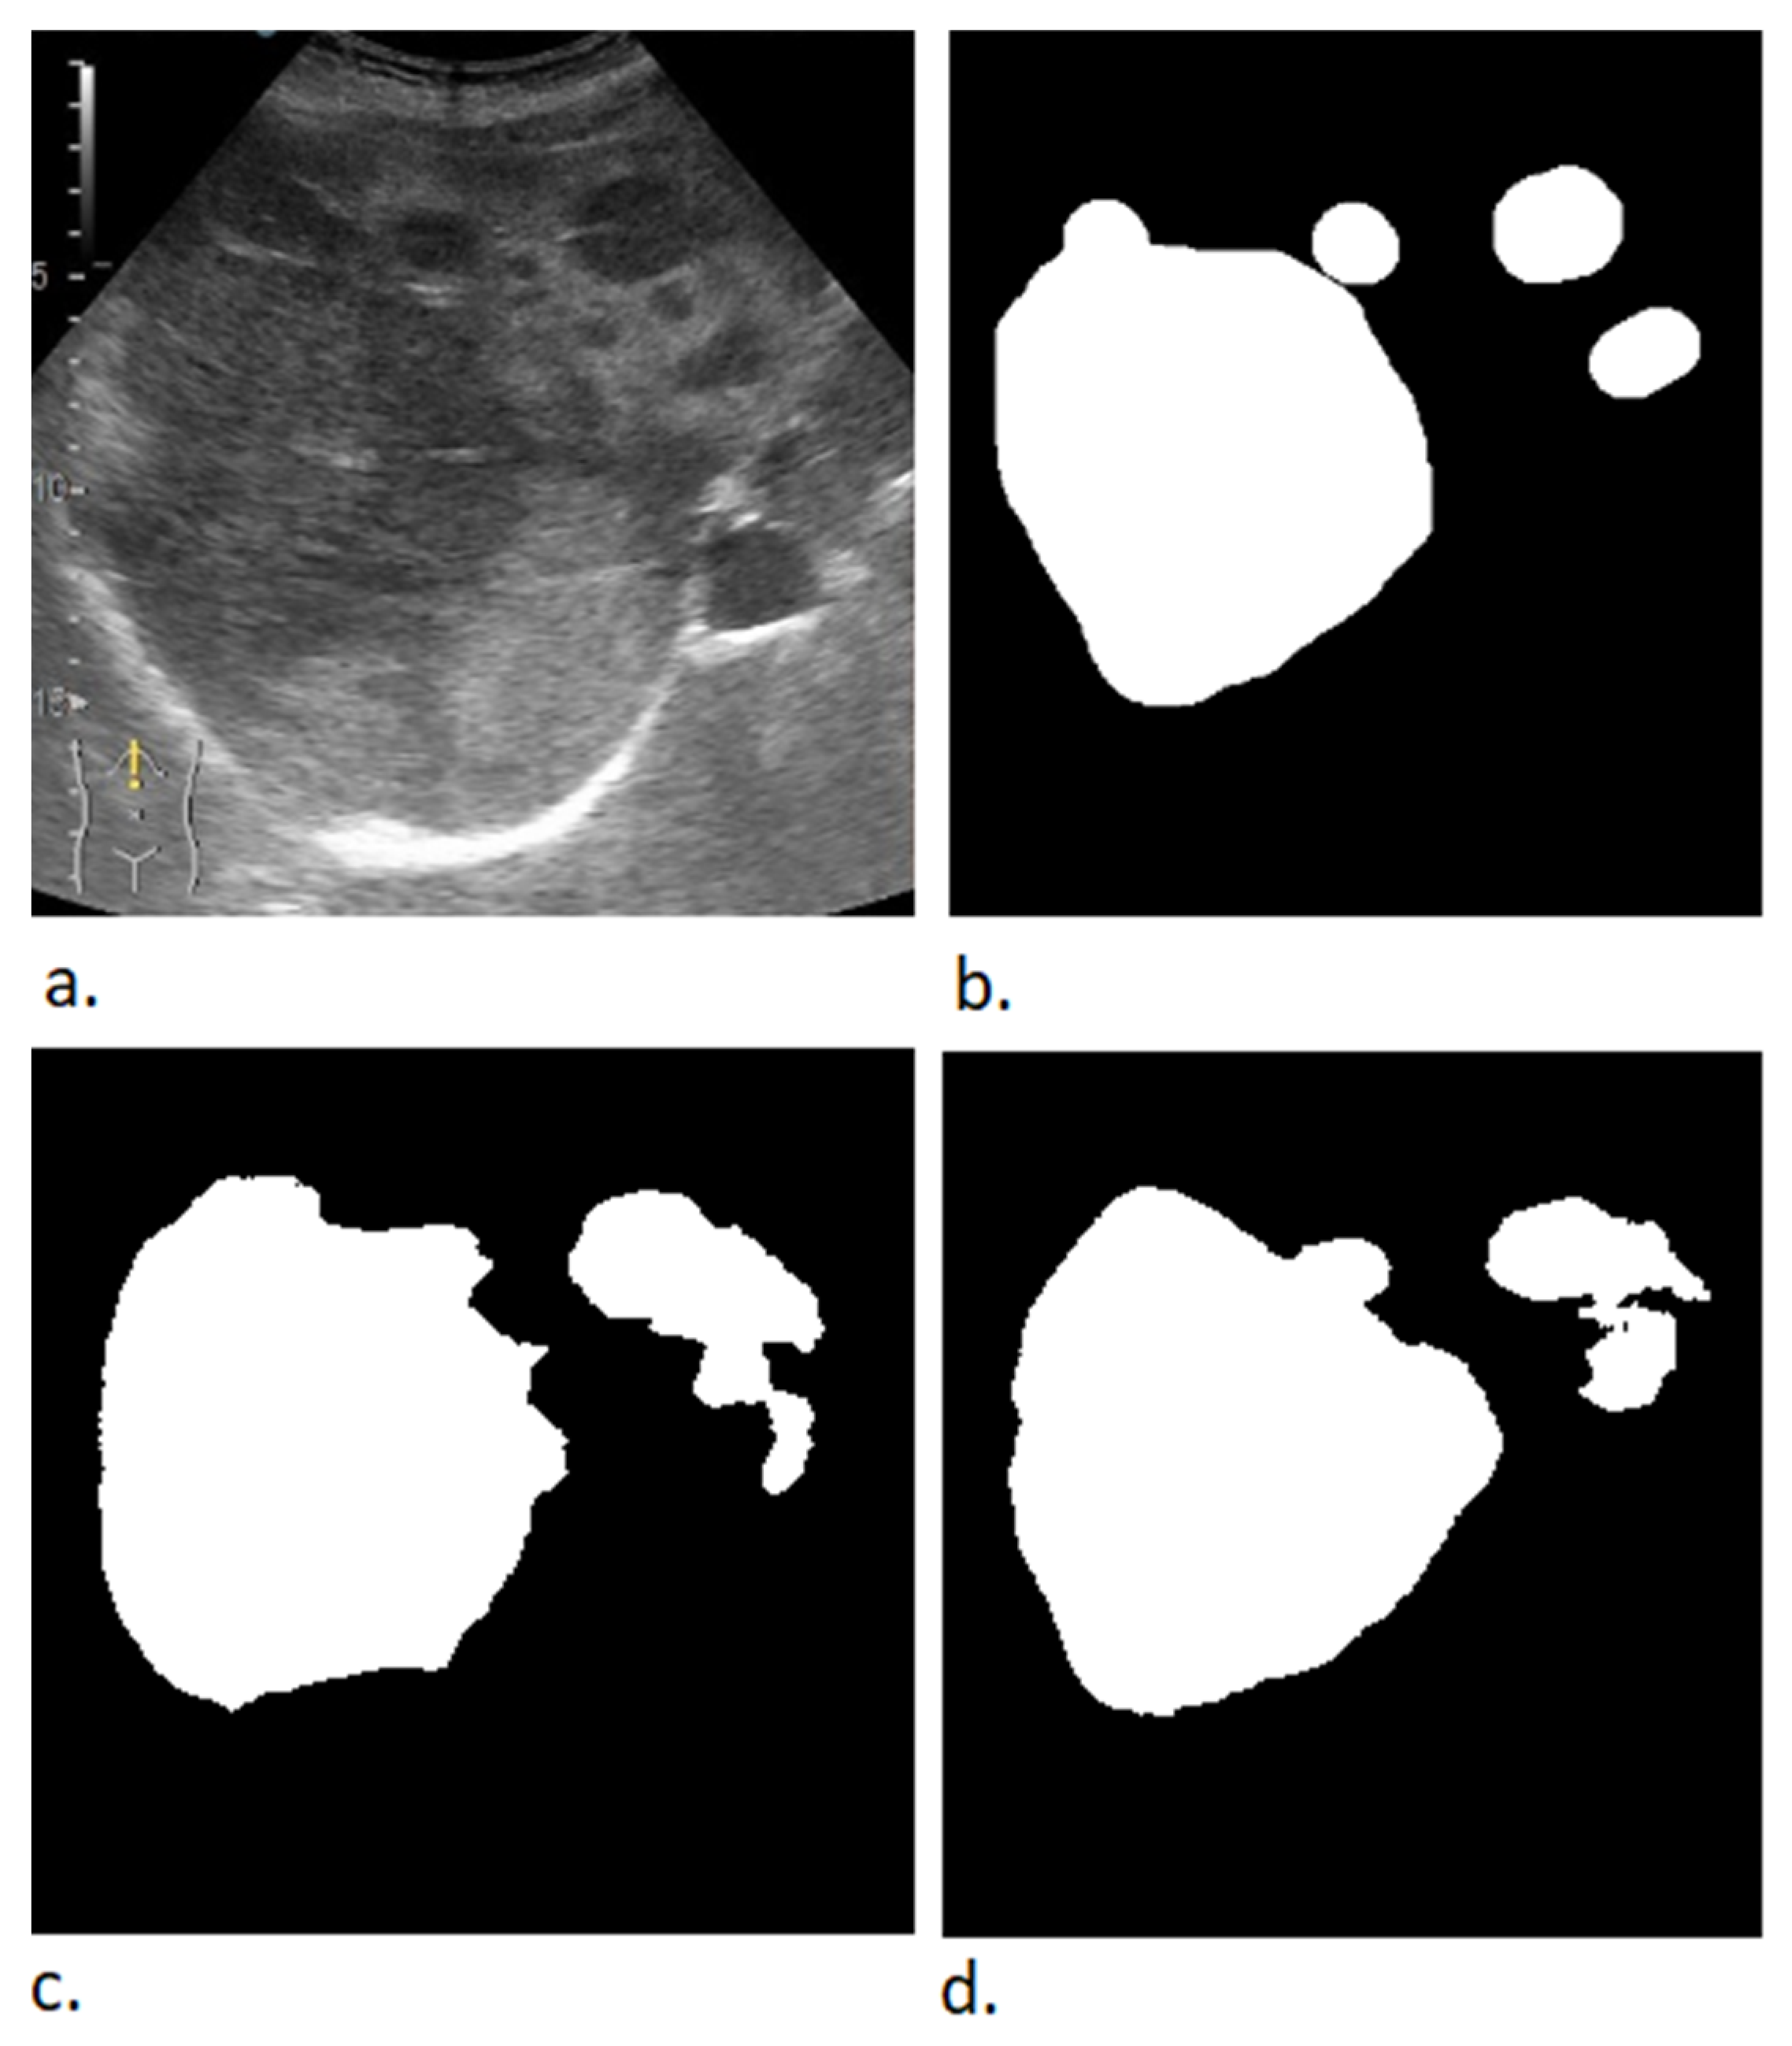

2.2. Data Preprocessing

| Algorithm 2. Mask creation (binary image) | |

| current_image ← obtain current image while current_image is not null do: mask ← new Image(current_image.width, current_image.height, values = 0) for each object in annotation_list do: roi ← object.getROI() roi.fill(values = 1) mask ← mask bitwise and roi mask_filename ← string concatenation (current_image.name, “-mask”) save image to disk (mask, mask_filename) | |